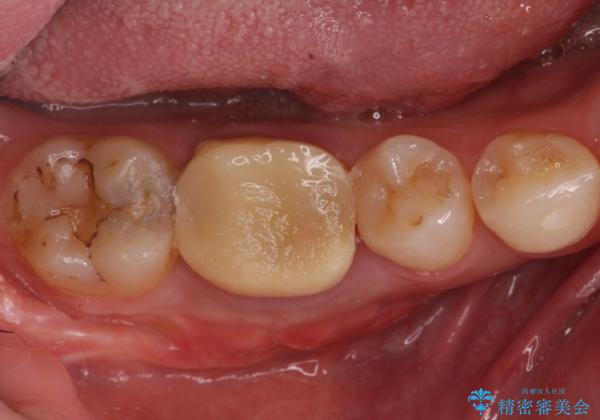

- 右下の奥歯がうずくとのことで来院されました。

根管治療を行った後、セラミックのかぶせ物を装着します。